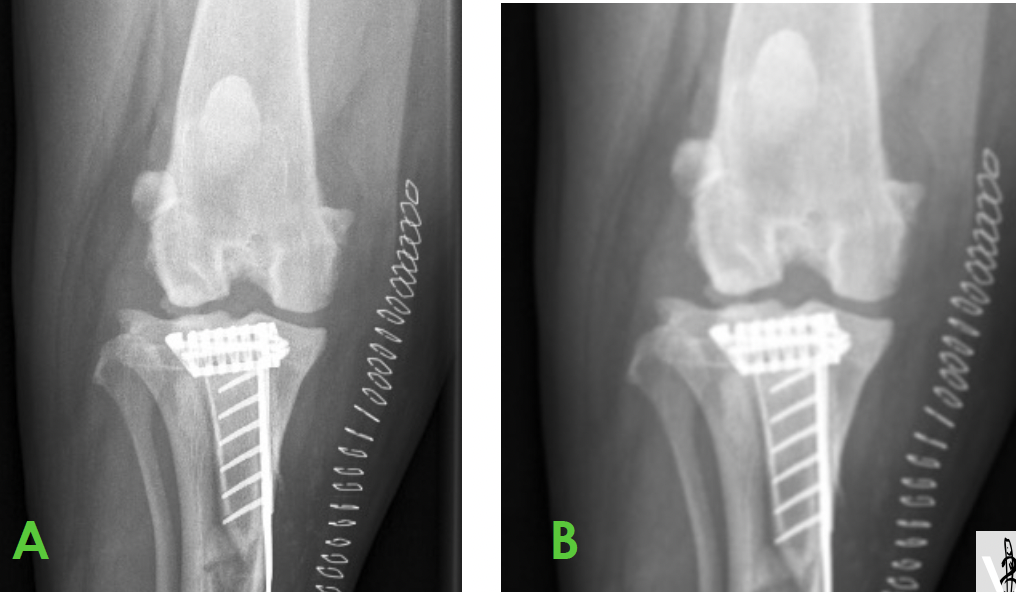

26

Cas 4: Cheval de 4 ans avec une chaleur importante au pied Je pense que le cheval a de la fourbure et pour le confirmer, je désire mesurer la distance entre la muraille et P3. Quelle ligne représente le mieux la distance désirée? 1. A 2. B 3. C 4. D

1. A **PIÈGE** Artéfact appelé uberschwinger; halo radiotransparent en périphérie des implants métalliques ou produit de contraste à une interface os-tissu mou